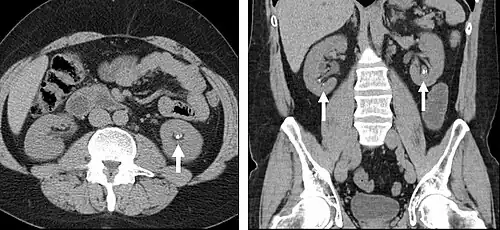

FIGURE 1. Non-contrast CT demonstrating multiple bilateral renal calculi (arrows), which can be obscured on contrast-enhanced images, particularly delayed images when there is excreted contrast in the renal collecting system; axial left, coronal reformat on right.

Non-contrast CT scans Figure 1a (left) and 1b (right) are of limited use for the differentiation of soft tissue structures. However, materials like blood, calcium (renal stones, vascular atherosclerosis), bone, and pulmonary parenchyma are highly visible and can usually be adequately assessed with non-contrast CT. For example, in the abdomen and pelvis, there are several indications for non-contrast imaging. These include: evaluation of renal calculi; assessment for gross intra-abdominal hemorrhage; and post-endostent volume measurements. In addition, non-contrast images are often obtained in conjunction with contrast enhanced images in evaluating potential renal transplant donors and in the evaluation of the pancreas (in combination with contrast phases). Of note, dual-energy CT and the development of virtual "non-contrast" images (VNC imaging) may ultimately obviate the combination scans. Additionally, CT angiography examinations performed for pathologies like aneurysms and dissection are frequently performed in conjunction with non-contrast imaging. The non-contrast images facilitate the differentiation of active extravasation or acute bleeding from vascular calcifications.